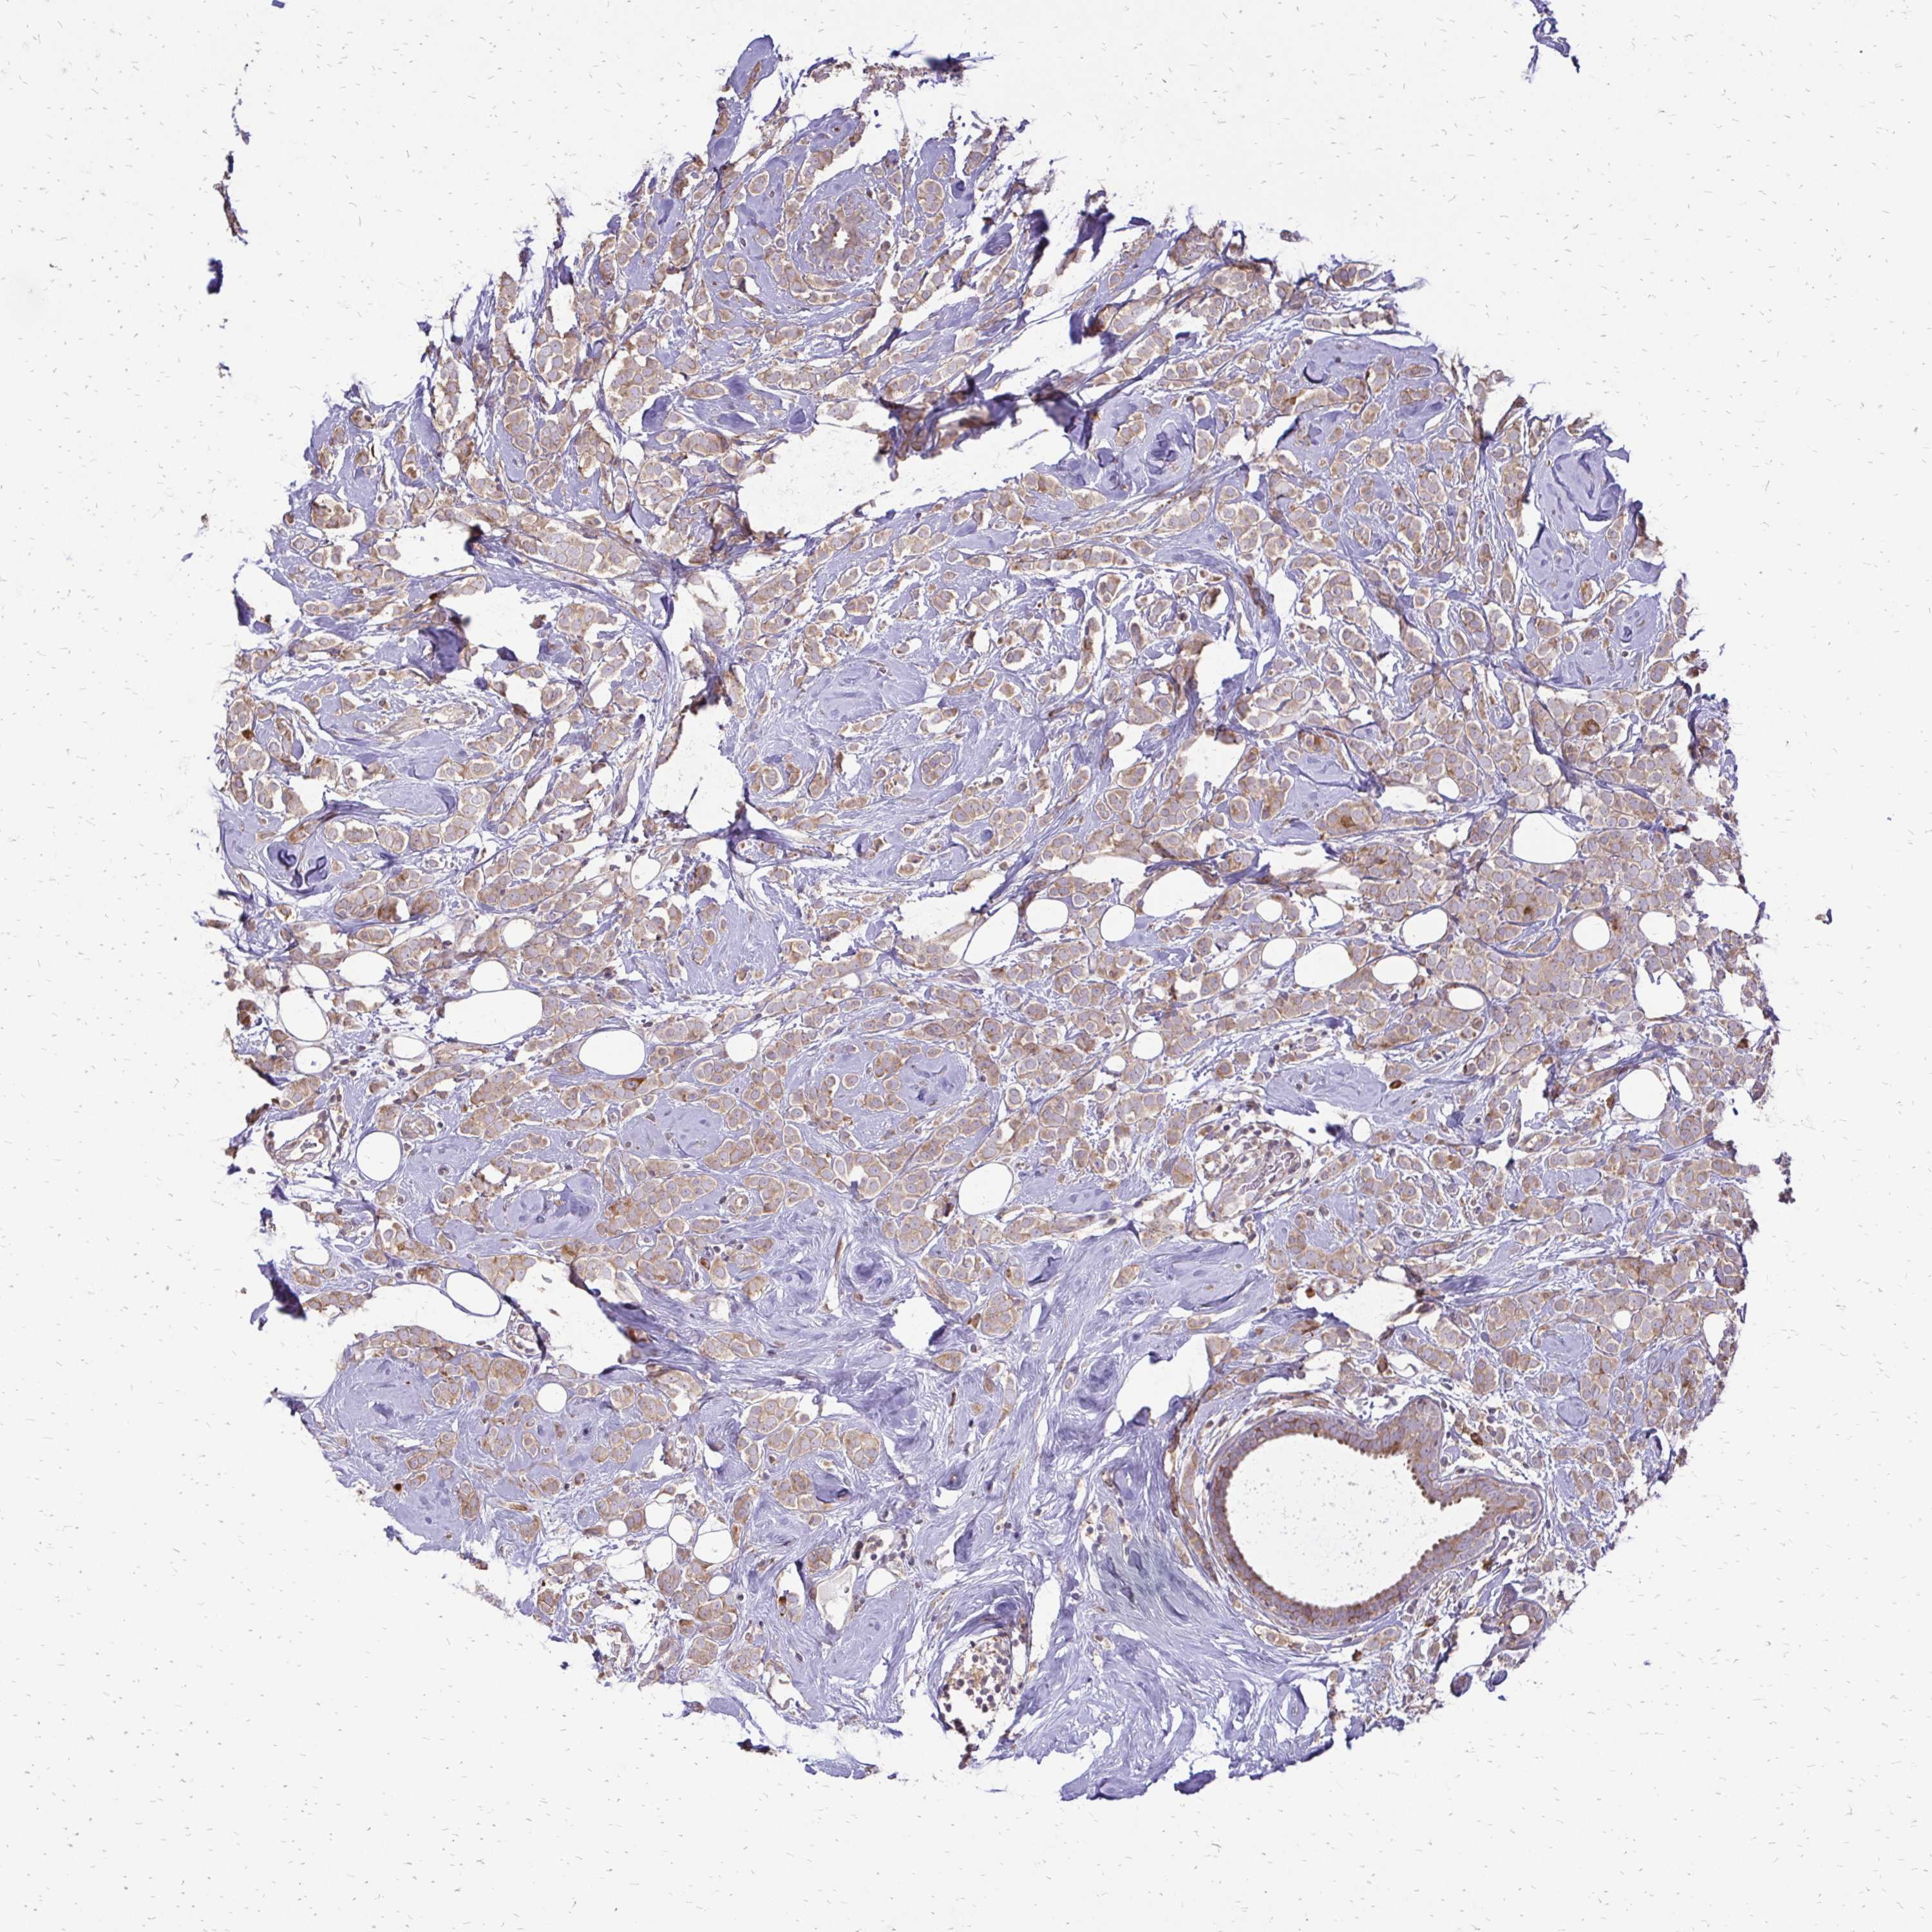

CANCER BREAST CANCER Show tissue menu

BRCA TCGA BRCA VALIDATION PROTEIN EXPRESSION

Breast cancer

Human cancer

Breast invasive carcinoma